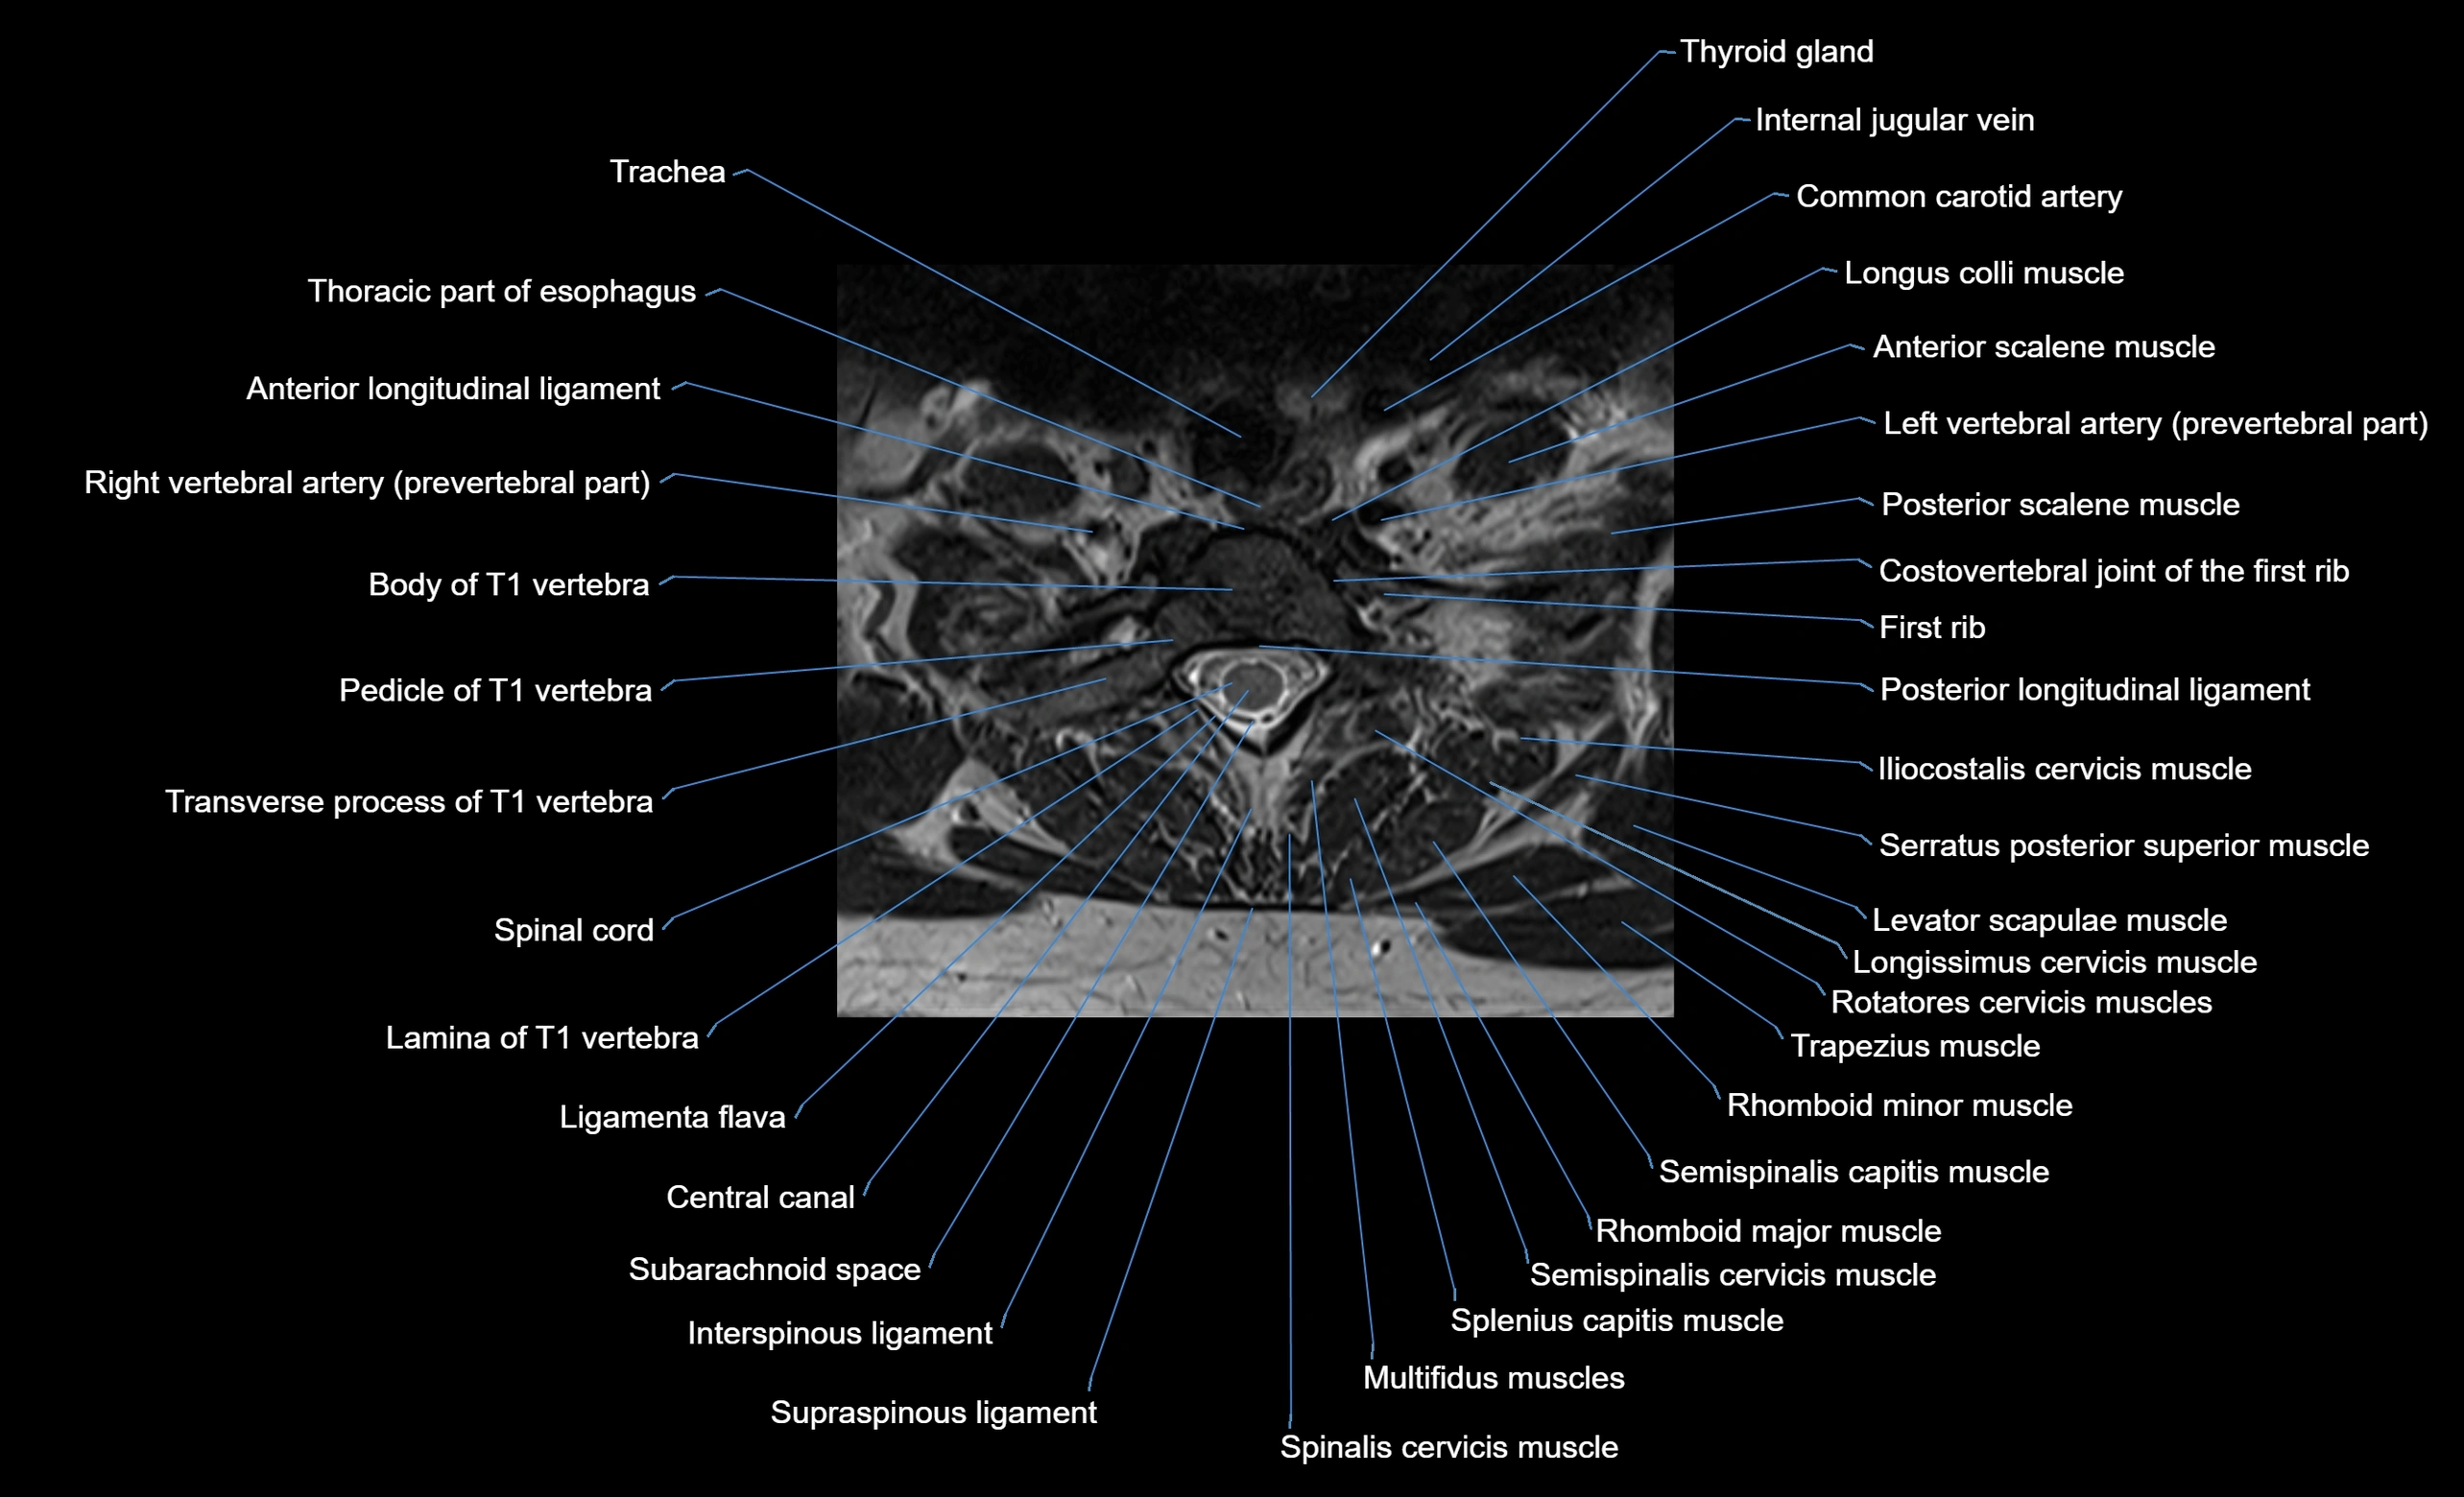

MRI image

image